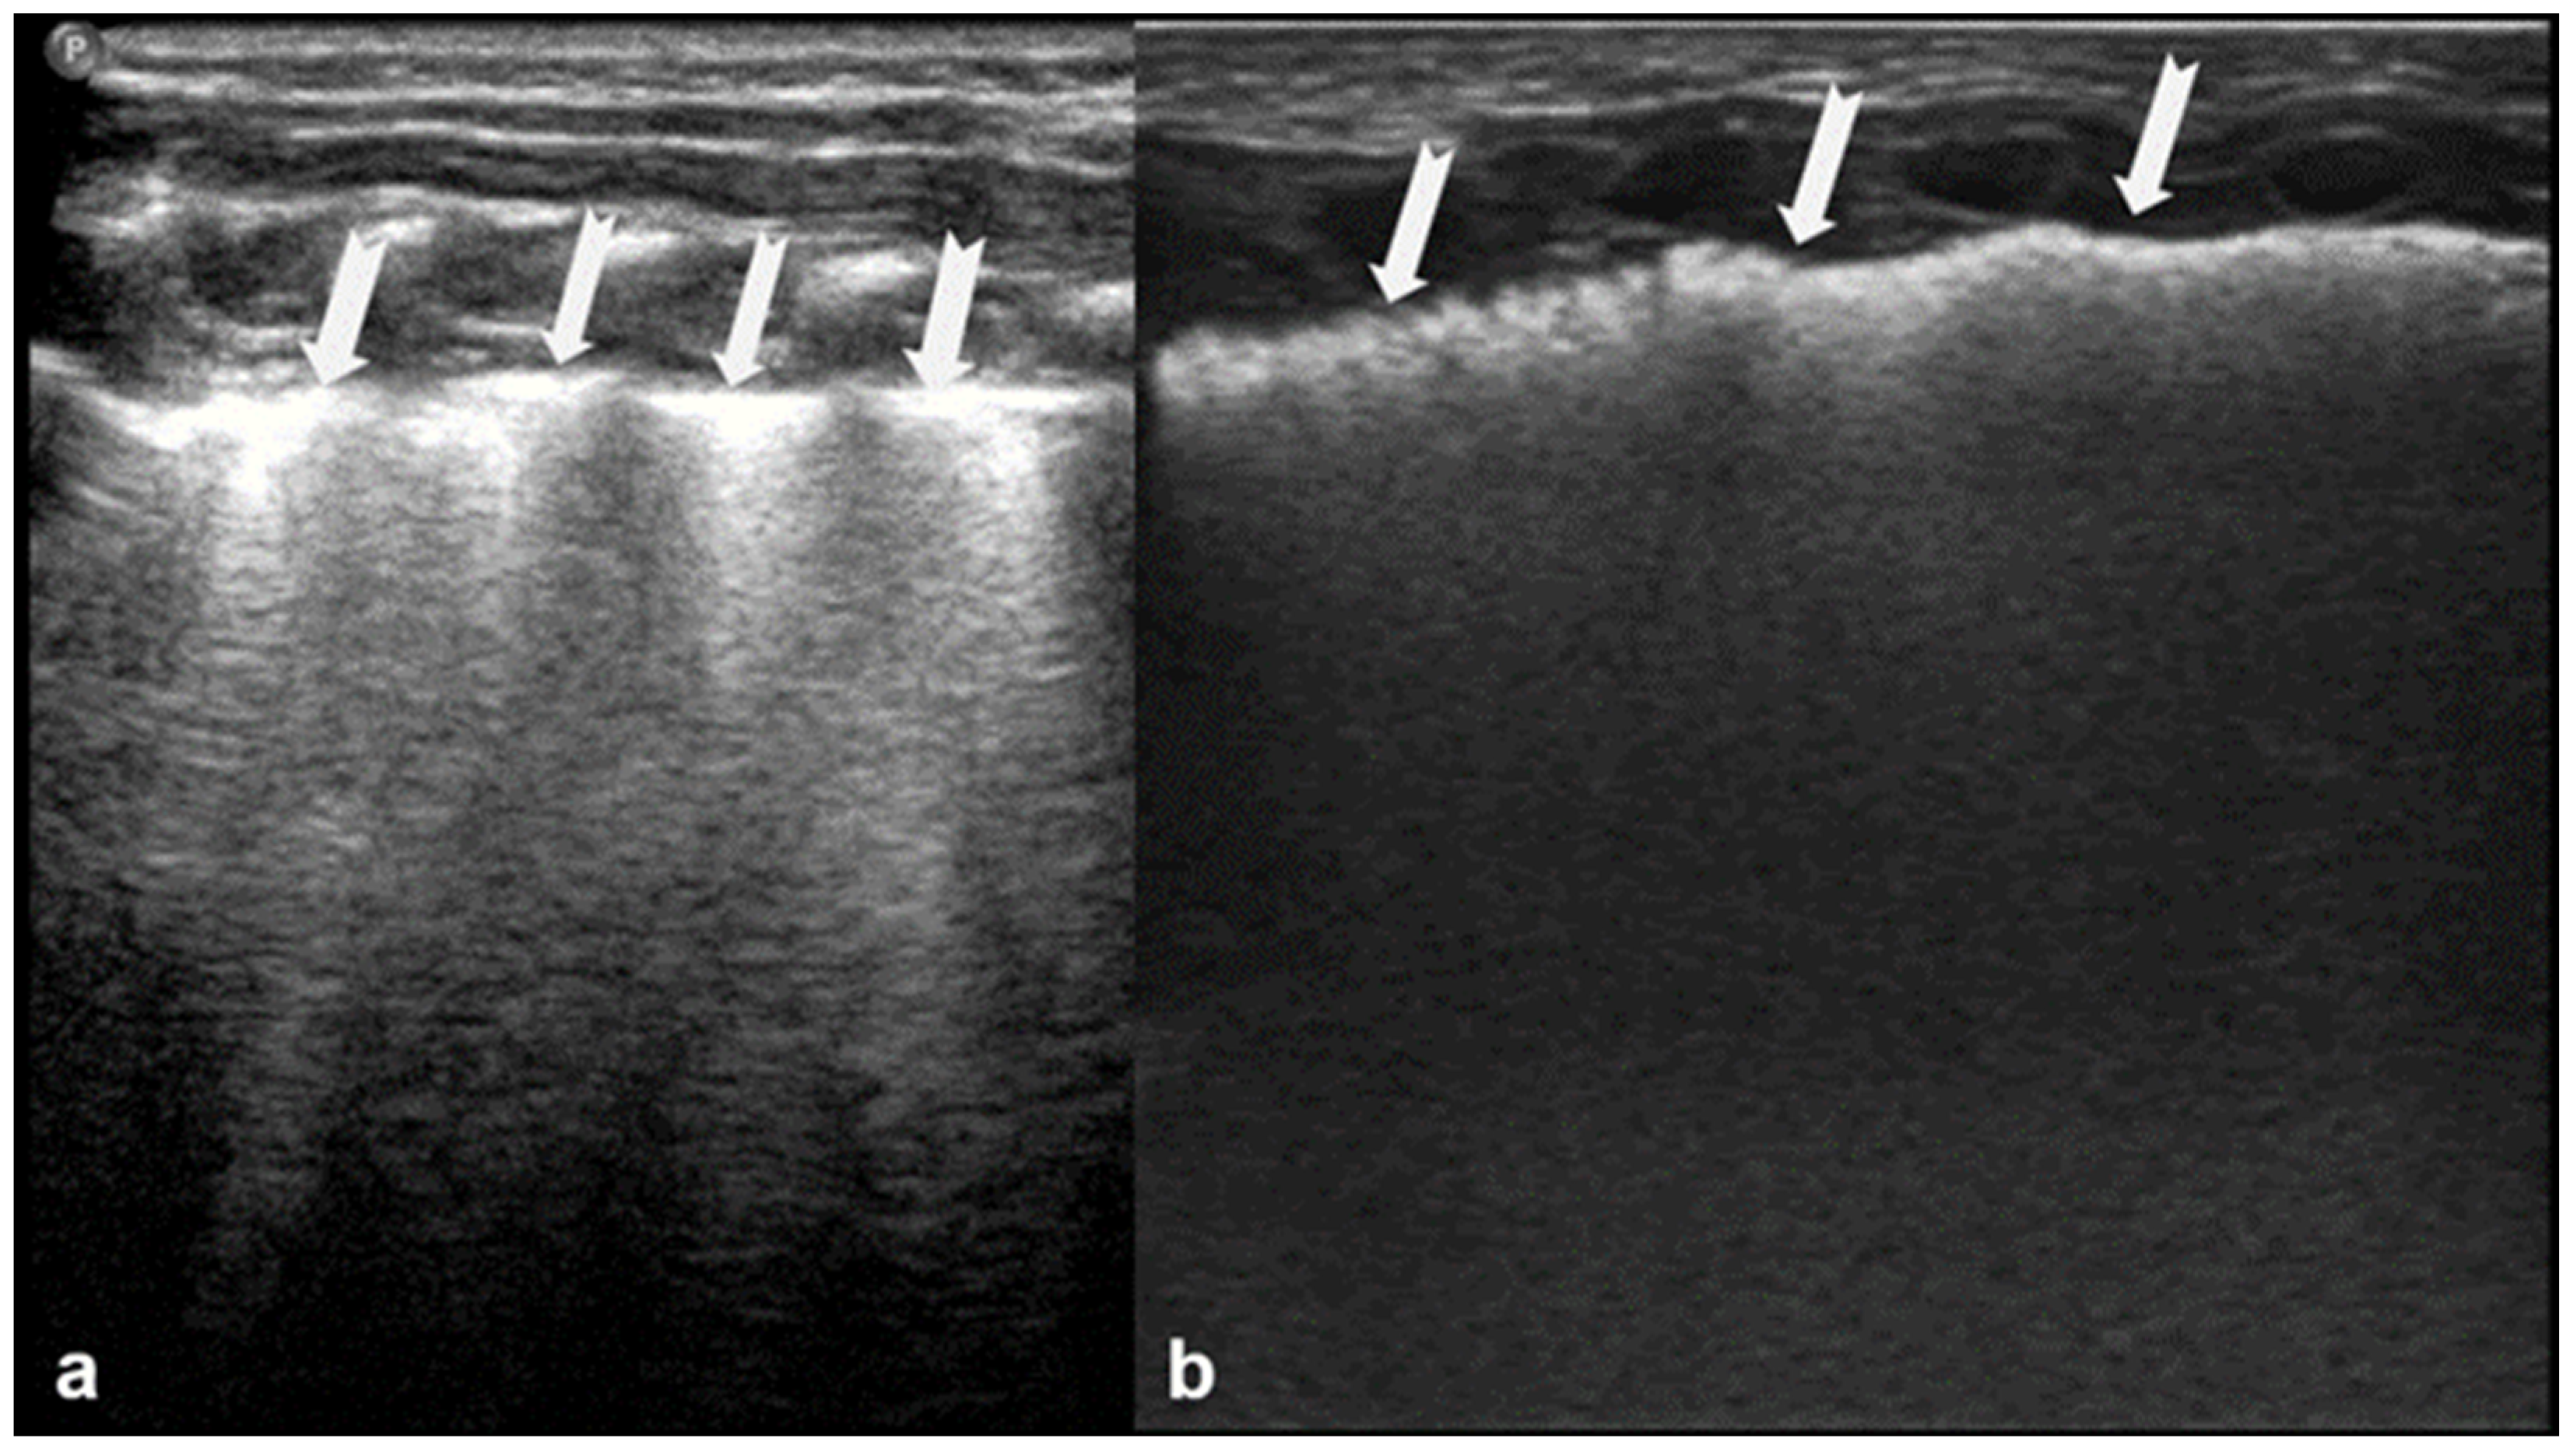

A-lines are horizontal, bright, echogenic lines that appear at equal intervals below the pleural line, running parallel to it (Figure 1). They are reverberation artifacts caused by the reflection of ultrasound waves between the pleura and the ultrasound probe. Although their presence typically indicates well-aerated, healthy lung tissue, A-lines can also be seen in certain pathological conditions, such as pneumothorax, where free air is present. Thus, A-lines are not always necessarily a sign of normal, healthy lungs [5,6,12,13,14,15,16].

Figure 1.

A-lines: Horizontal, bright, echogenic lines at equal intervals below the pleural line, running parallel to it. A-Lines are one of the main (basic) artifacts in LUS.

B-lines are vertical reverberation-like hyperechoic artifacts seen during LUS imaging which originate from the pleural line and extend to the bottom of the imaging field without fading in intensity (Figure 2a). B-line artifacts move in synchrony with lung sliding and intersect horizontal A-lines, effectively obscuring them. Their presence is typically associated with fluid accumulation in the alveoli or interstitial space, and they are commonly referred to as ultrasound lung comets. However, B-lines are frequently observed in neonates and can appear as a normal finding within the first 24 to 48 h after birth [13,14,17]. During LUS imaging, identification of up to two B-lines at the lung base is considered to be normal, while the presence of three or more B-lines between the intercostal space in a single view is considered significant and indicative of an underlying pathology. If multiple B-lines are identified by LUS, then the patient likely suffers from interstitial syndrome. When the air content in the lungs decreases, the number of lines tends to increase, because of the associated increase in lung density. Moreover, when the identified B-lines are confluent, this is an indication that the alveoli are filled with sub-pleural fluid. When interstitial edema is present, the presence or absence of B-lines can guide the administration of fluids [16,17,18,19]. However, it should be noted that B-lines are absent in the aforementioned pneumothorax.

Figure 2.

B-lines: Vertical reverberation-like hyperechoic artifacts originate from the pleural line and extend to the bottom of the image (a). This artifact could be normal (<3 in an intercostal space) or abnormal when are more than three, multiple or coalescent B-lines (b).